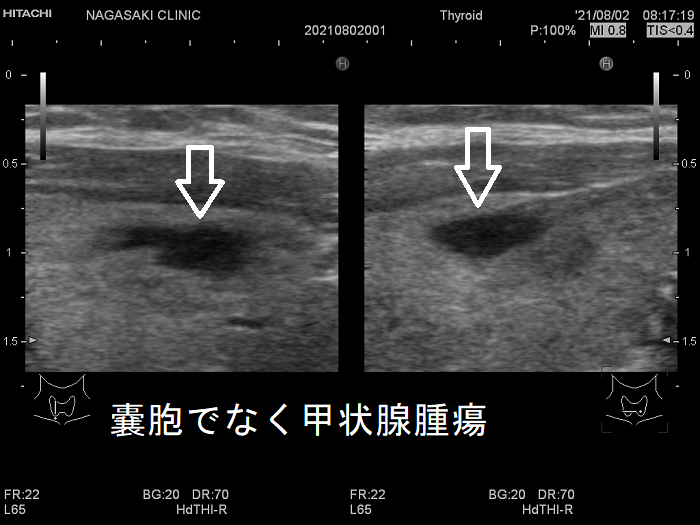

甲状腺のう胞に見えるが実は甲状腺腫瘍

甲状腺のう胞(甲状腺嚢胞)に見えるが甲状腺腫瘍 超音波(エコー)画像;低エコー(真っ黒)で、内部にコロイド様物質があるように見えるため、甲状腺のう胞(甲状腺嚢胞)と間違えます。

甲状腺のう胞に見えるが実は甲状腺腫瘍 eFlow

甲状腺のう胞(甲状腺嚢胞)でなく甲状腺腫瘍  eFlow(イー フロー);内部血流が、はっきり見えて甲状腺腫瘍なのがわかります。